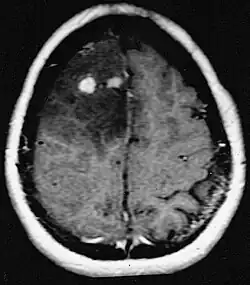

Os pacientes sofrem de uma variedade de sintomas característicos de uma lesão maciça focal ou multifocal. A RM geralmente mostra tumores com realce homogêneo de contraste dentro da substância branca periventricular profunda. Multifocalidade e realce não homogêneo são típicos para pacientes com sistema imunológico enfraquecido. A análise do linfoma do SNC é extremamente importante no diagnóstico diferencial das neoplasias cerebrais. Ressalta-se que a administração de corticosteróides pode levar ao desaparecimento completo do realce, dificultando o diagnóstico das lesões. Consequentemente, se o linfoma do SNC for considerado no diagnóstico diferencial, os corticosteróides devem ser evitados, a menos que o efeito de massa cause um problema sério e imediato no paciente.

As metástases cerebrais são as neoplasias intracranianas mais comuns em adultos, sendo dez vezes mais comuns que os tumores cerebrais primários. Eles pisam em 20 até 40 por cento dos adultos com câncer e estão associados principalmente ao câncer de pulmão e mama e melanoma . Essas lesões resultam da disseminação de células cancerígenas pela corrente sanguínea e ocorrem mais comumente na junção da substância cinzenta e branca, onde a seção transversal dos vasos sanguíneos se altera, aprisionando embolias de células tumorais . 80 por cento das lesões ocorrem nos hemisférios cerebrais, 15 por cento no cerebelo e 5 por cento no tronco cerebral. Cerca de 80 por cento dos pacientes têm história de câncer sistêmico e 70 por cento têm múltiplas metástases cerebrais.

Avanços significativos foram feitos recentemente no diagnóstico e tratamento dessas lesões, resultando em melhora da sobrevida e controle dos sintomas. O início dos sinais e sintomas é semelhante ao de outras lesões maciças no cérebro. O método diagnóstico de escolha é a ressonância magnética com meio de contraste.

A literatura mostra resultados equivalentes para cirurgia e radiocirurgia. Este último parece ser mais conveniente, eficaz e seguro para lesões pequenas ou em regiões inacessíveis à cirurgia. A radiocirurgia é uma alternativa sensata para pacientes que não podem ser operados por razões médicas. No entanto, a cirurgia é claramente o método ideal para obter tecidos para diagnóstico e remover as lesões que causam efeito de massa. Portanto, a radiocirurgia e a cirurgia devem ser melhor consideradas como dois métodos complementares, mas diferentes a serem aplicados, dependendo da situação diferente do paciente. Por quase 50 por cento dos pacientes com uma ou duas metástases cerebrais não são candidatos à remoção cirúrgica devido à inacessibilidade das lesões, extensão da doença sistêmica ou outros fatores. Esses e outros pacientes com metástases múltiplas geralmente recebem radioterapia panencefálica como padrão de tratamento. Na verdade, chegar até quase 50 por cento deles com esta terapia uma melhora nos sintomas neurológicos e 50 até 70 por cento uma reação perceptível. A quimioterapia raramente é usada principalmente para metástases cerebrais.